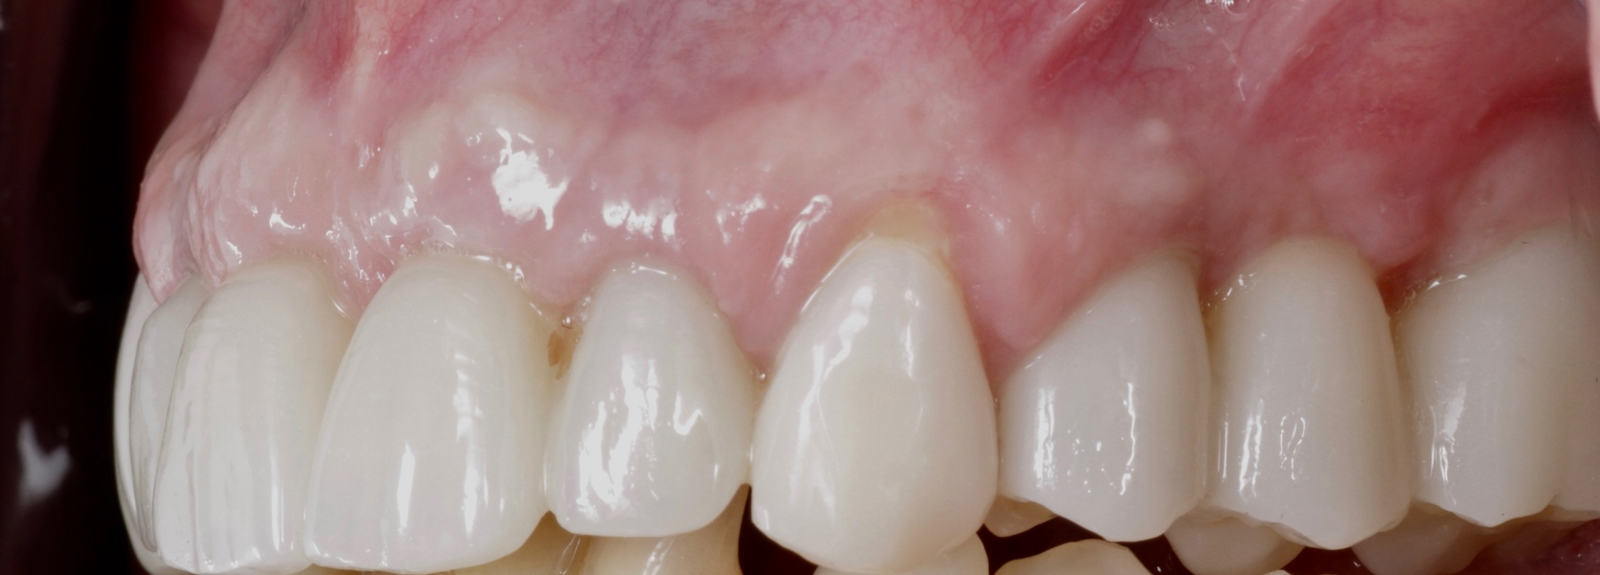

Definitive prosthetic treatment was performed after completion of implant healing with three CAD/CAM-fabricated monolithic zirconia bridges (DD cubeX2, Dental Direkt). The bridges were screwed on to BEGO titanium base abutments (Figs. 14–16). Good fit of the prosthetic superstructures was displayed in the radiograph after placement (Fig. 17). The two-year follow-up examination in July 2019 revealed excellent aesthetic and clinical soft-tissue conditions (Figs. 18–20). No radiographic bone loss had occurred at the implant sites (Fig. 21). Neither the submerged central incisors nor the distobuccal molar root displayed any signs of periapical inflammation, and the patient reported no complications. The patient’s oral hygiene had improved significantly during the follow-up period.

Fig. 18: Frontal aspect of the restorations after the two-year follow-up period.

Fig. 19: Right lateral aspect of the restorations after the two-year follow-up period

Fig. 20: Left lateral aspect of the restorations after the two-year follow-up period.